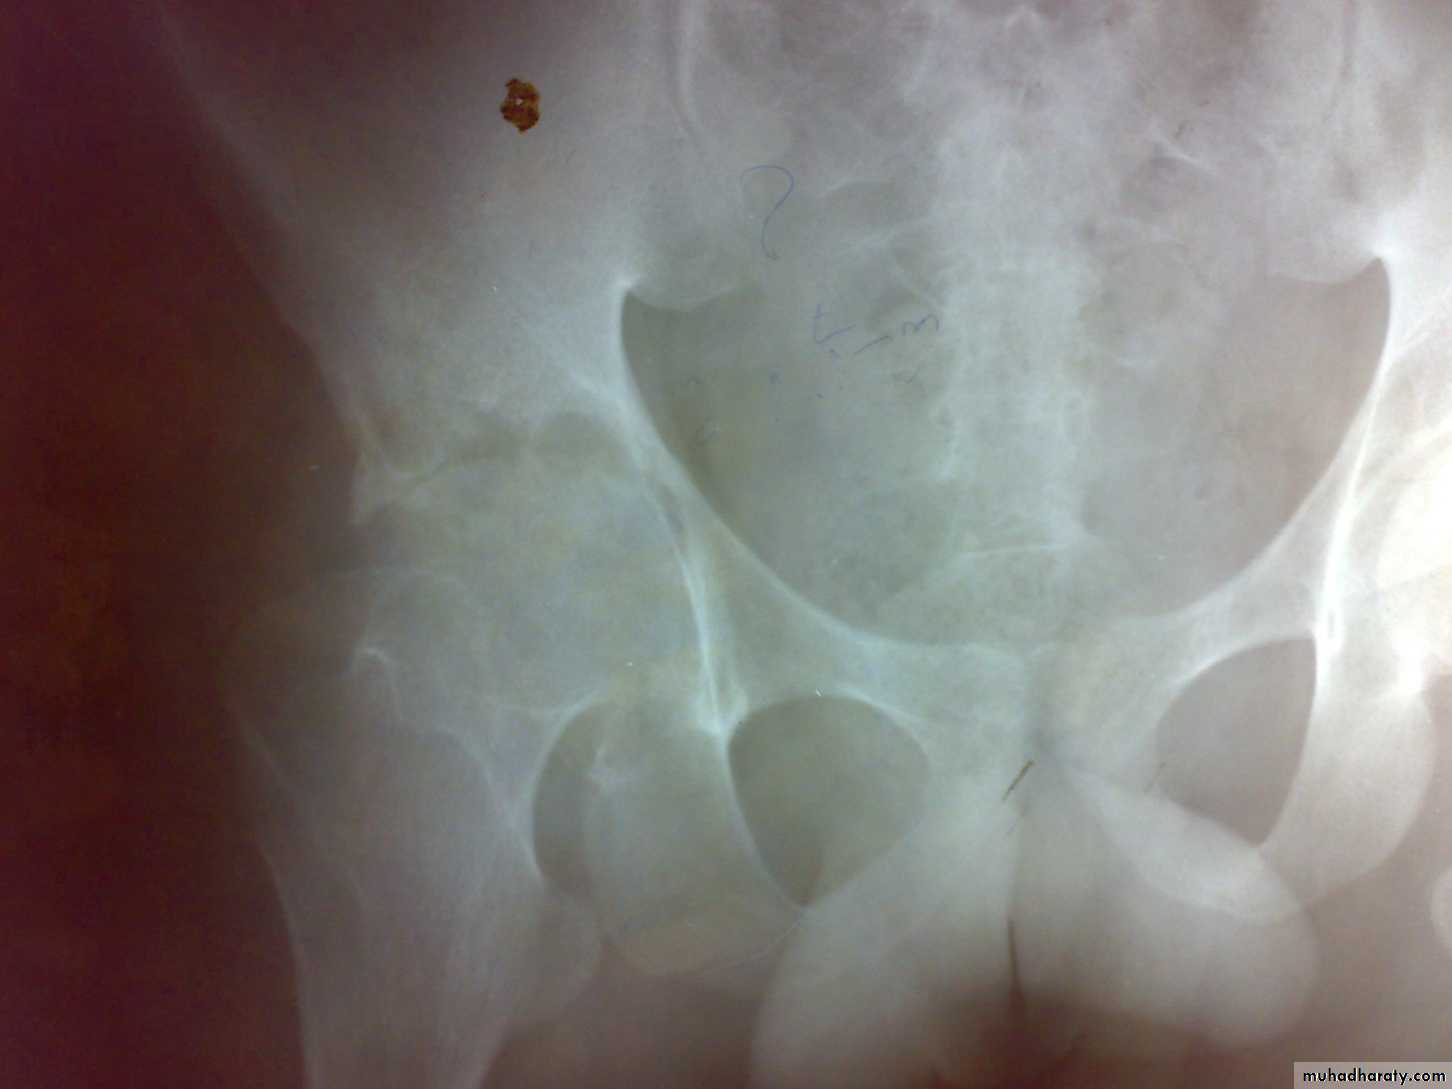

Radiological features

early changes:

Soft tissue swelling, Periarticular osteoporosis

Loclized osteoprosis (Bone ends ‘washed – out’ or localized decalcification ).

Narrowing and irregularity of the articular ends.

Late changes:

Erosions of the subarticular cartilage.

cystic changes appeared.